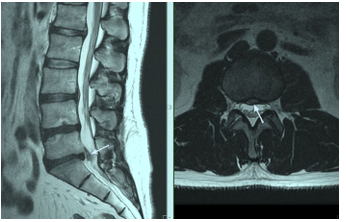

Ultrasonographic Evaluation of Lumbar Intervertebral Discs Hernia Detected by MRI in High School Aged Children

Rizvan Yagubovich Abdullaiev, Igor A Voronzhev, Roman R Abdullaiev and Nataly S Lisenko. 18(2): 01-08.